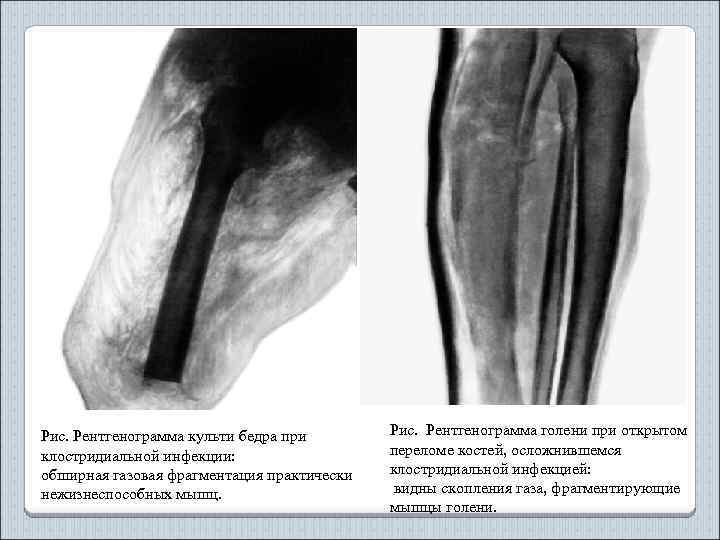

Рис. Рентгенограмма культи бедра при клостридиальной инфекции: обширная газовая фрагментация практически нежизнеспособных мышц. Рис. Рентгенограмма голени при открытом переломе костей, осложнившемся клостридиальной инфекцией: видны скопления газа, фрагментирующие мышцы голени.